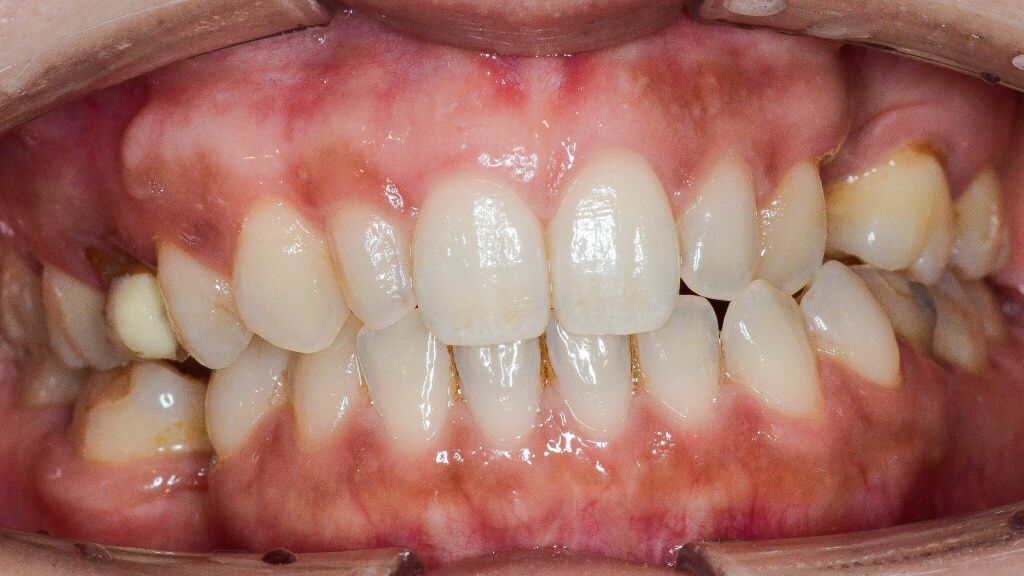

2.術前正面

さらに歯並びの問題として、左上の2番・3番の歯が下の歯よりも内側に位置している「クロスバイト(反対咬合)」の状態でした。

4.術前正面クロスバイト